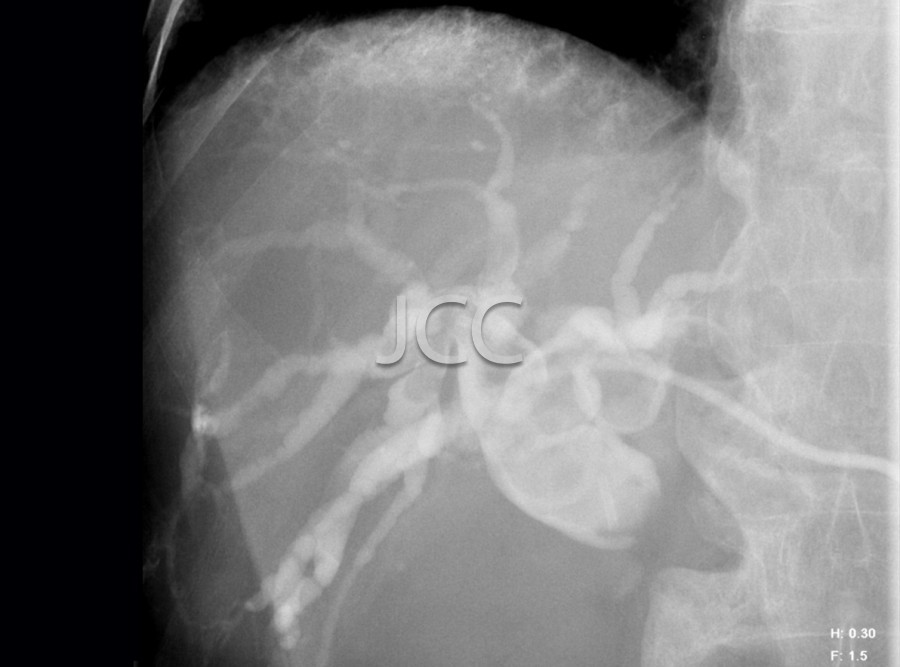

Radiologia de Intervenção - Drenagem Biliar